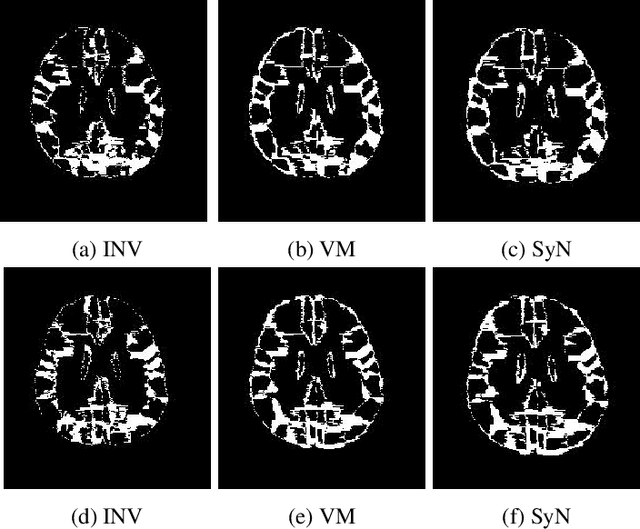

Abstract:The recent application of deep learning technologies in medical image registration has exponentially decreased the registration time and gradually increased registration accuracy when compared to their traditional counterparts. Most of the learning-based registration approaches considers this task as a one directional problem. As a result, only correspondence from the moving image to the target image is considered. However, in some medical procedures bidirectional registration is required to be performed. Unlike other learning-based registration, we propose a registration framework with inverse consistency. The proposed method simultaneously learns forward transformation and backward transformation in an unsupervised manner. We perform training and testing of the method on the publicly available LPBA40 MRI dataset and demonstrate strong performance than baseline registration methods.

Abstract:The recent application of Deep Learning in various areas of medical image analysis has brought excellent performance gain. The application of deep learning technologies in medical image registration successfully outperformed traditional optimization based registration algorithms both in registration time and accuracy. In this paper, we present a densely connected convolutional architecture for deformable image registration. The training of the network is unsupervised and does not require ground-truth deformation or any synthetic deformation as a label. The proposed architecture is trained and tested on two different version of tissue cleared data, 10\% and 25\% resolution of high resolution dataset respectively and demonstrated comparable registration performance with the state-of-the-art ANTS registration method. The proposed method is also compared with the deep-learning based Voxelmorph registration method. Due to the memory limitation, original voxelmorph can work at most 15\% resolution of Tissue cleared data. For rigorous experimental comparison we developed a patch-based version of Voxelmorph network, and trained it on 10\% and 25\% resolution. In both resolution, proposed DenseDeformation network outperformed Voxelmorph in registration accuracy.

Abstract:Image registration plays an important role in comparing images. It is particularly important in analyzing medical images like CT, MRI, PET, etc. to quantify different biological samples, to monitor disease progression and to fuse different modalities to support better diagnosis. The recent emergence of tissue clearing protocols enable us to take images at cellular level resolution. Image registration tools developed for other modalities are currently unable to manage images of such extreme high resolution. The recent popularity of deep learning based methods in the computer vision community justifies a rigorous investigation of deep-learning based methods on tissue cleared images along with their traditional counterparts. In this paper, we investigate and compare the performance of a deep learning based registration method with traditional optimization based methods on samples from tissue-clearing methods. From the comparative results it is found that a deep-learning based method outperforms all traditional registration tools in terms of registration time and has achieved promising registration accuracy.

Abstract:Recent progress in tissue clearing has allowed for the imaging of entire organs at single-cell resolution. These methods produce very large 3D images (several gigabytes for a whole mouse brain). A necessary step in analysing these images is registration across samples. Existing methods of registration were developed for lower resolution image modalities (e.g. MRI) and it is unclear whether their performance and accuracy is satisfactory at this larger scale. In this study, we used data from different mouse brains cleared with the CUBIC protocol to evaluate five freely available image registration tools. We used several performance metrics to assess accuracy, and completion time as a measure of efficiency. The results of this evaluation suggest that the ANTS registration tool provides the best registration accuracy while Elastix has the highest computational efficiency among the methods with an acceptable accuracy. The results also highlight the need to develop new registration methods optimised for these high-resolution 3D images.